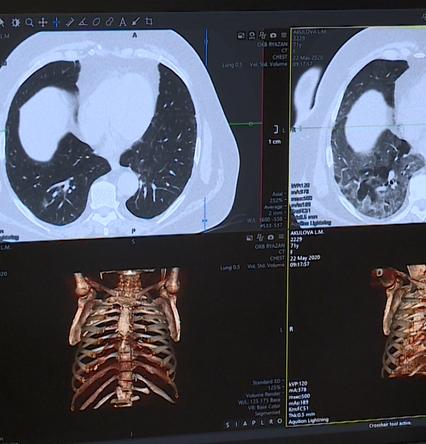

Минздрав призвал не делать компьютерную томографию «на всякий случай»

Врачи настоятельно рекомендуют воздержаться от визитов в медучреждения чтобы сделать КТ в целях профилактики.